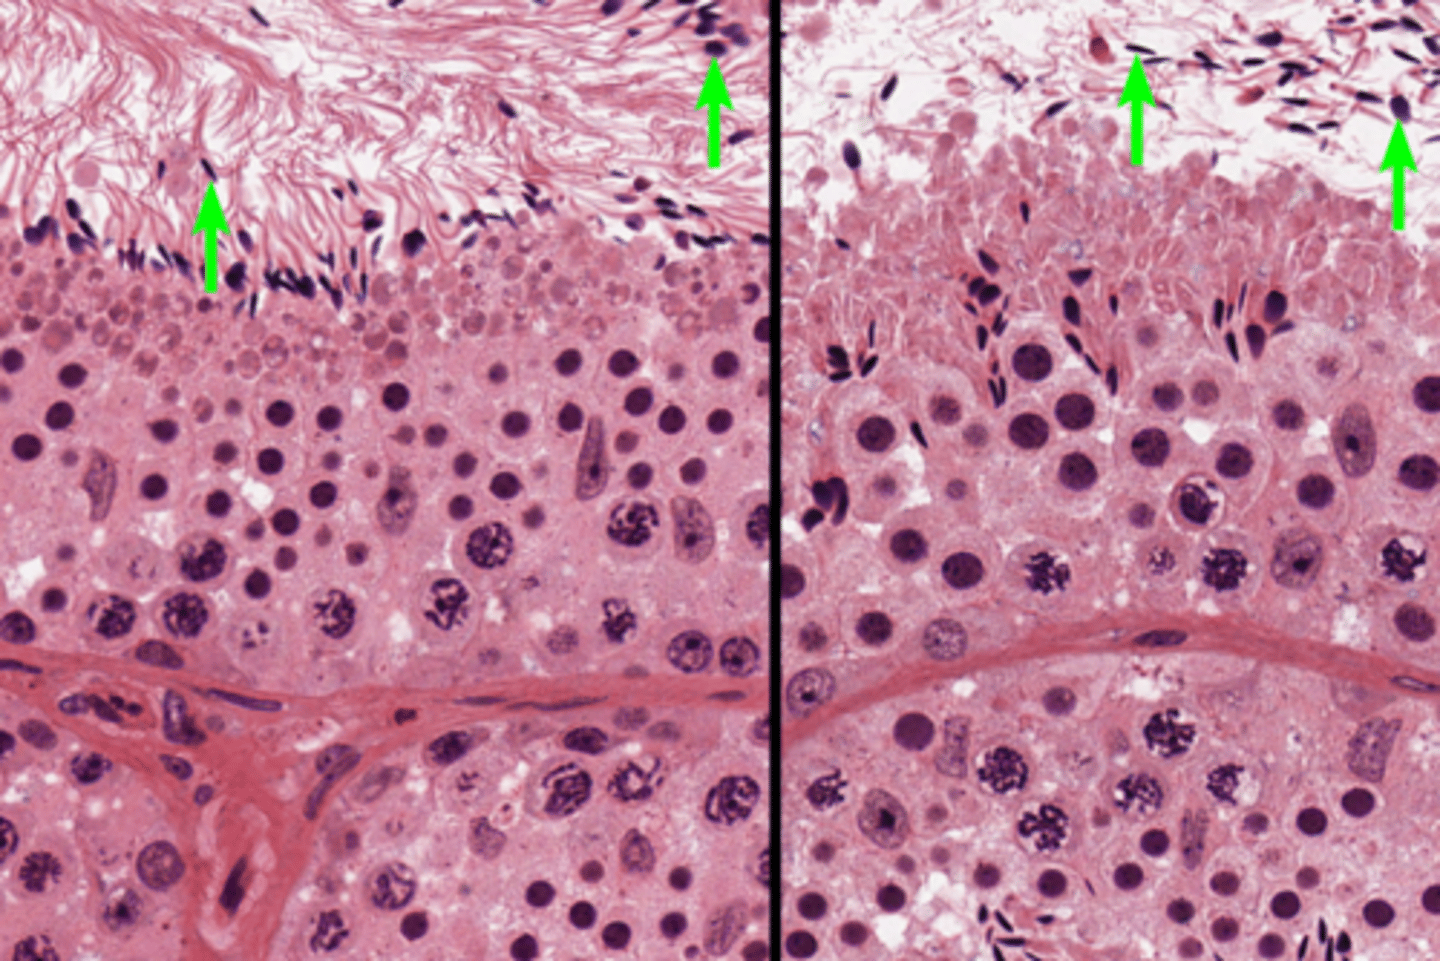

Seminiferous tubules

Seminiferous tubules

Seminiferous tubules

Spermatogenesis

Spermatogenesis

Spermatogonia

Primary spermatocyte

Spermatogonia

Spermatid (early)

Primary spermatocyte

Spermatid (late)

Spermatid (early)

Spermatozoon

Spermatid (late)

Spermatozoa